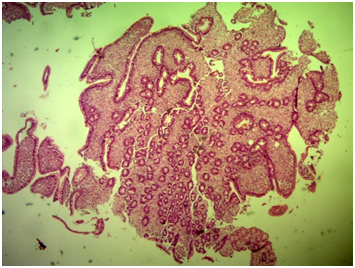

Laboratory tests: Hemoglobin 10mg %, hematocrit 31 %, HIV serology negative. Chest and abdominal CT scans showed bilateral pleural effusions and moderate ascites. Stool search for ova and parasites was negative, and steatocrit was normal. The patient underwent a colonoscopy in which polyps have been found and removed. An upper endoscopy with duodenal biopsies was performed. The histological examination of biopsies showed macrophages with a granular cytoplasma and PAS positive inclusions, compatible with Whipple's disease (Figures 1–4). In the absence of molecular biology test to further confirm the diagnosis, we began treatment with ceftriaxone, with a progressive improvement in the number of bowel movements and the general condition of the patient. After discharge, he continued on sulfamethoxazole and trimethoprim for a year. Medication was discontinued after one year and the patient is asymptomatic.

Figure 2 Duodenal mucosa with preserved villous architecture and diffuse infiltrate of macrophages in the lamina propria (HE 40x).

Figure 3 Duodenal mucosa with preserved villous architecture and diffuse infiltrate of macrophages in the lamina propria (HE 100x).